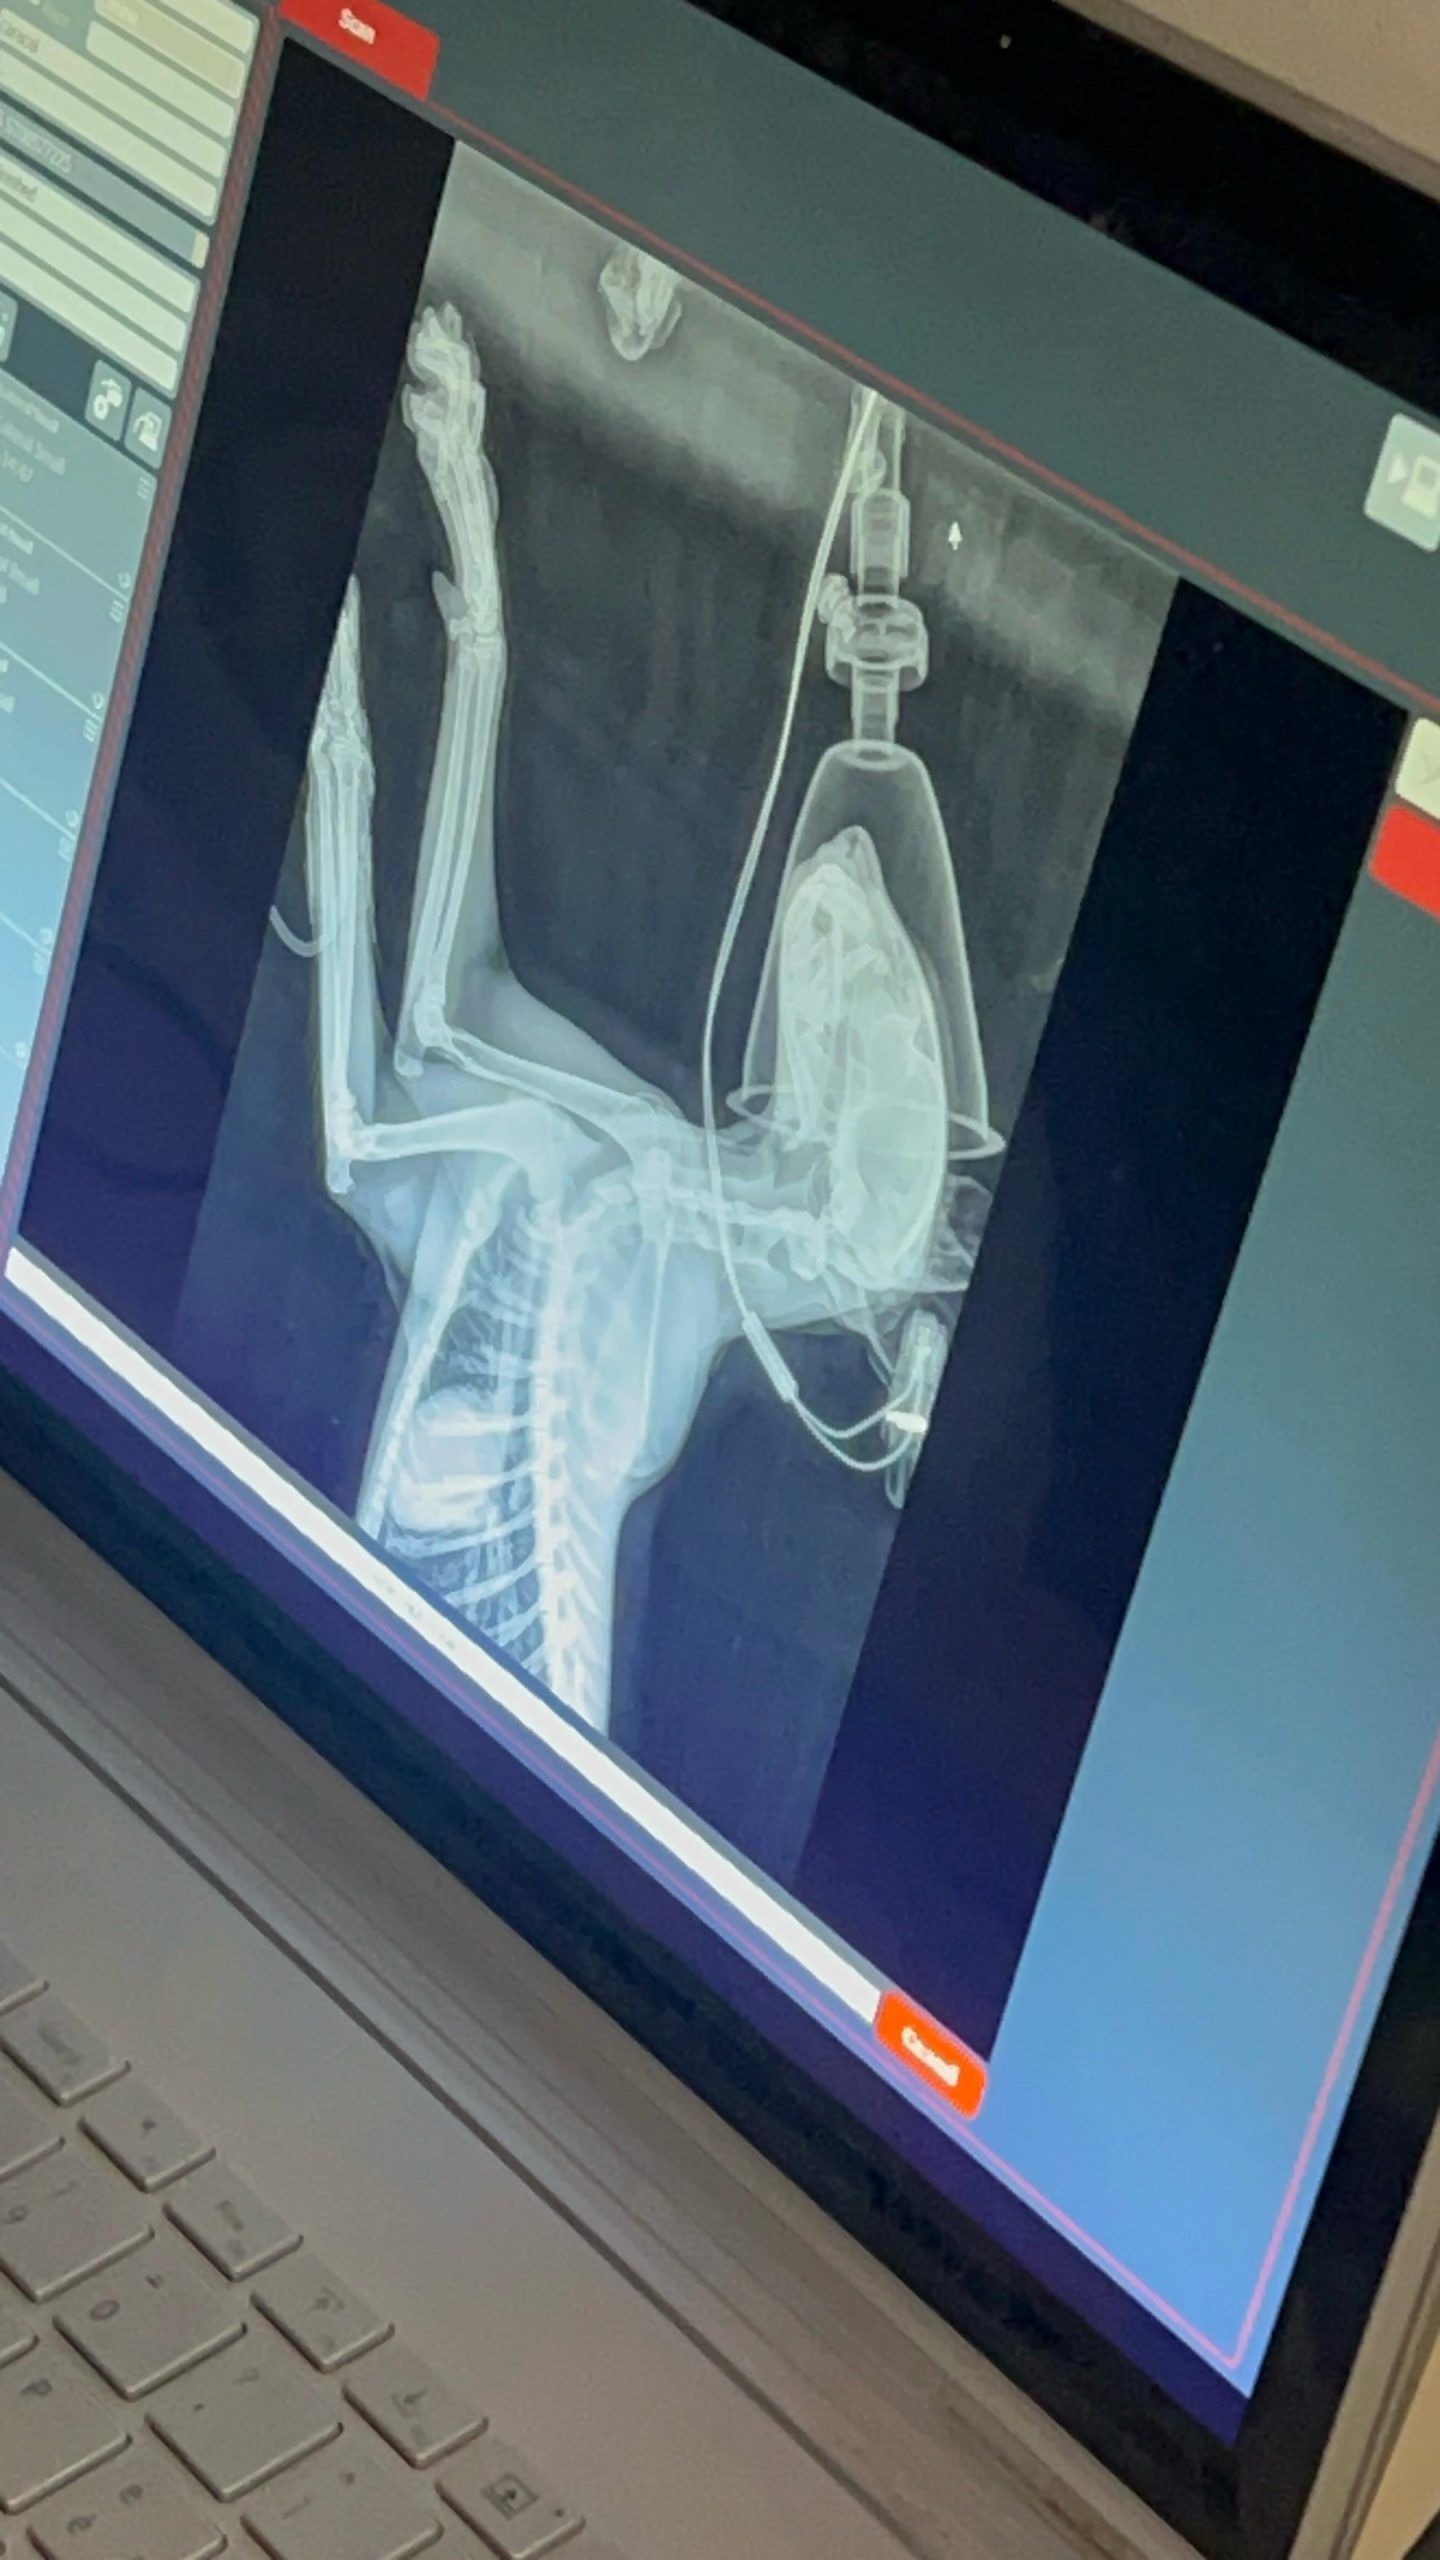

לדברי פרופסור דודו אשחר, מנהל בית החולים לחיות בר שבספארי: "הקרקלית הגיעה במצב גופני ירוד כשהיא רזה מאוד, אפאטית ועם צליעה קשה באחת מרגליה האחוריות. במקביל לבדיקות דם כלליות נערכו לה צילומי רנטגן מקיפים שהראו שבר קטן בעצם החזה, חלוק אבן קטן שבלעה והבעיה העיקרית שראינו הייתה שבר ישן קרוב לברך שהתאחה לחלוטין בצורה לא טבעית. דבר שיכול להסביר את הצליעה הקשה ממה היא סובלת".